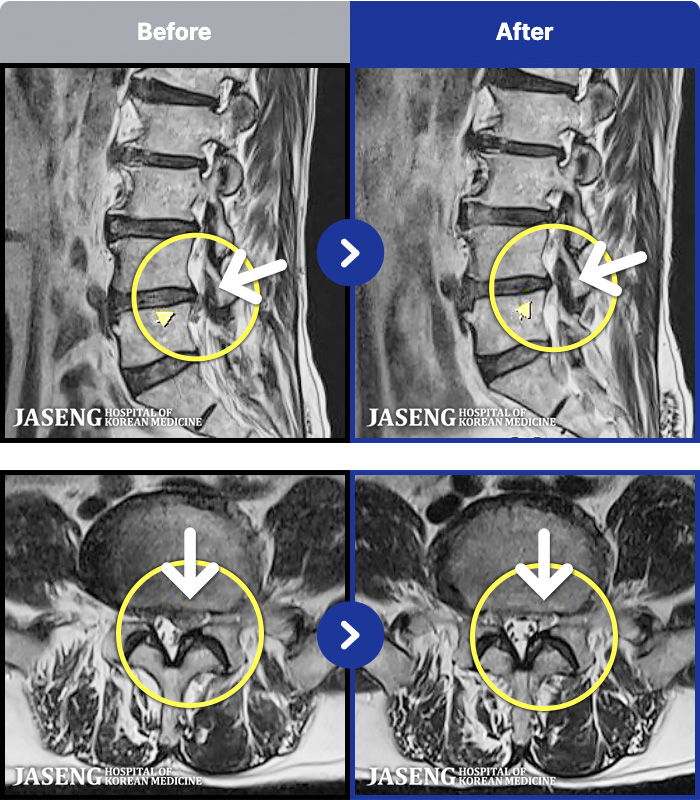

- MRI ġ

MRI ġ

1,304 MRI ũ ʸ Ȯϼ.